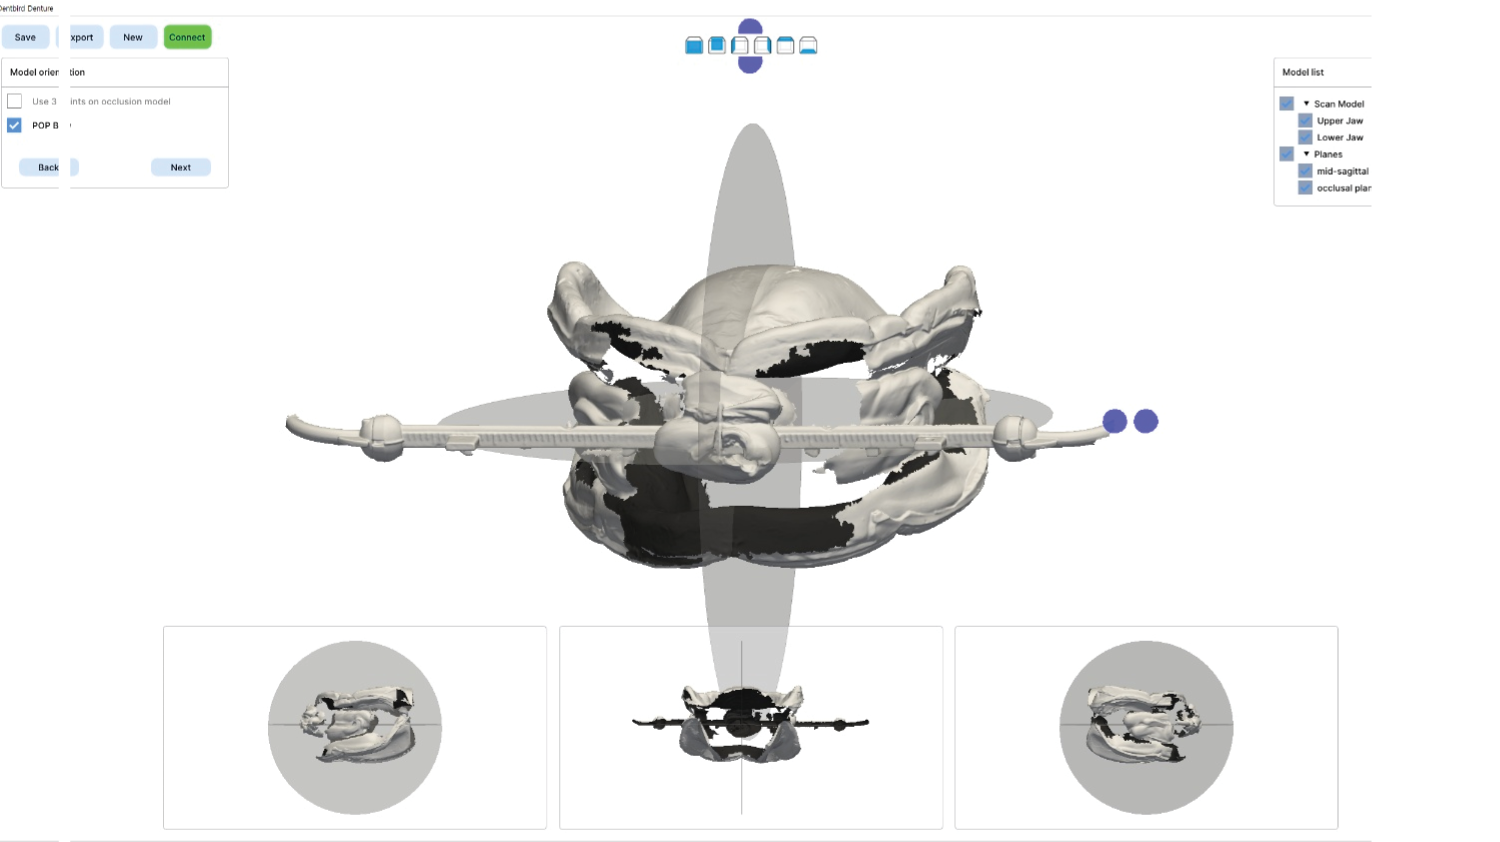

The program also introduces the JB Fork system, which integrates CBCT imaging and anterior reference points to enable one-step surgical stent fabrication without repeated impressions. Through practical demonstrations, attendees will see how this approach streamlines implant surgery while maintaining accuracy. The course concludes with insights into plasma surface treatment in implantology, highlighting its role in advancing clinical outcomes.

The program also introduces the JB Fork system, which integrates CBCT imaging and anterior reference points to enable one-step surgical stent fabrication without repeated impressions. Through practical demonstrations, attendees will see how this approach streamlines implant surgery while maintaining accuracy. The course concludes with insights into plasma surface treatment in implantology, highlighting its role in advancing clinical outcomes.

Part 2

One-Step Surgical Stent Fabrication with JB Fork

• Radiopaque JB Fork and the role of six anterior reference points: Registration with CBCT and integration with facial scanners

• One-step avatar creation without additional clinical procedures

• Surgical stent design and its application in implant surgery

• Live demonstration of JB Fork application in a patient case

Digital denture design and related lecture (DT Jang), lab procedure after this lecture |

JB fork application lecture (Prof Huh) |

| 03:30PM – 04:00PM |

Real patient application and taking CBCT, JB fork scanning(Prof Huh) |

| 04:00PM – 05:00PM |

Surgical stent design with all guides and implant studio software. (Prof Huh) |

Part 2

One-Step Surgical Stent Fabrication with JB Fork

• Radiopaque JB Fork and the role of six anterior reference points: Registration with CBCT and integration with facial scanners

• One-step avatar creation without additional clinical procedures

• Surgical stent design and its application in implant surgery

• Live demonstration of JB Fork application in a patient case

01:00 PM – 02:30 PM

Digital denture design and related lecture (DT Jang), lab procedure after this lecture

02:30 PM – 03:30 PM

JB fork application lecture (Prof Huh)

03:30 PM – 04:00 PM

Real patient application and taking CBCT, JB fork scanning(Prof Huh)

04:00 PM – 05:00 PM

Surgical stent design with all guides and implant studio software. (Prof Huh)